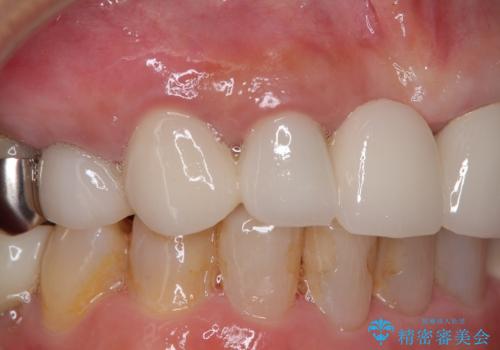

周辺の歯は20年以上前に装着したクラウンで、色合いや形態が気になっているとのことで、オールセラミックブリッジにて補綴治療を行うこととしました。

まずは土台の歯を引っぱり出し、外科処置により歯肉の状態を十分に整えた上で、オールセラミッククラウンにて補綴することとしました。

元々の土台は歯肉の中に埋もれており、歯肉が著しく腫れている状態だったため、歯を引っぱり出すこととしました。引っぱる期間は2ヶ月ほどで済み、その後歯周外科処置を行ったことで、土台周りの歯肉は腫脹のない健全な状態へと改善されました。